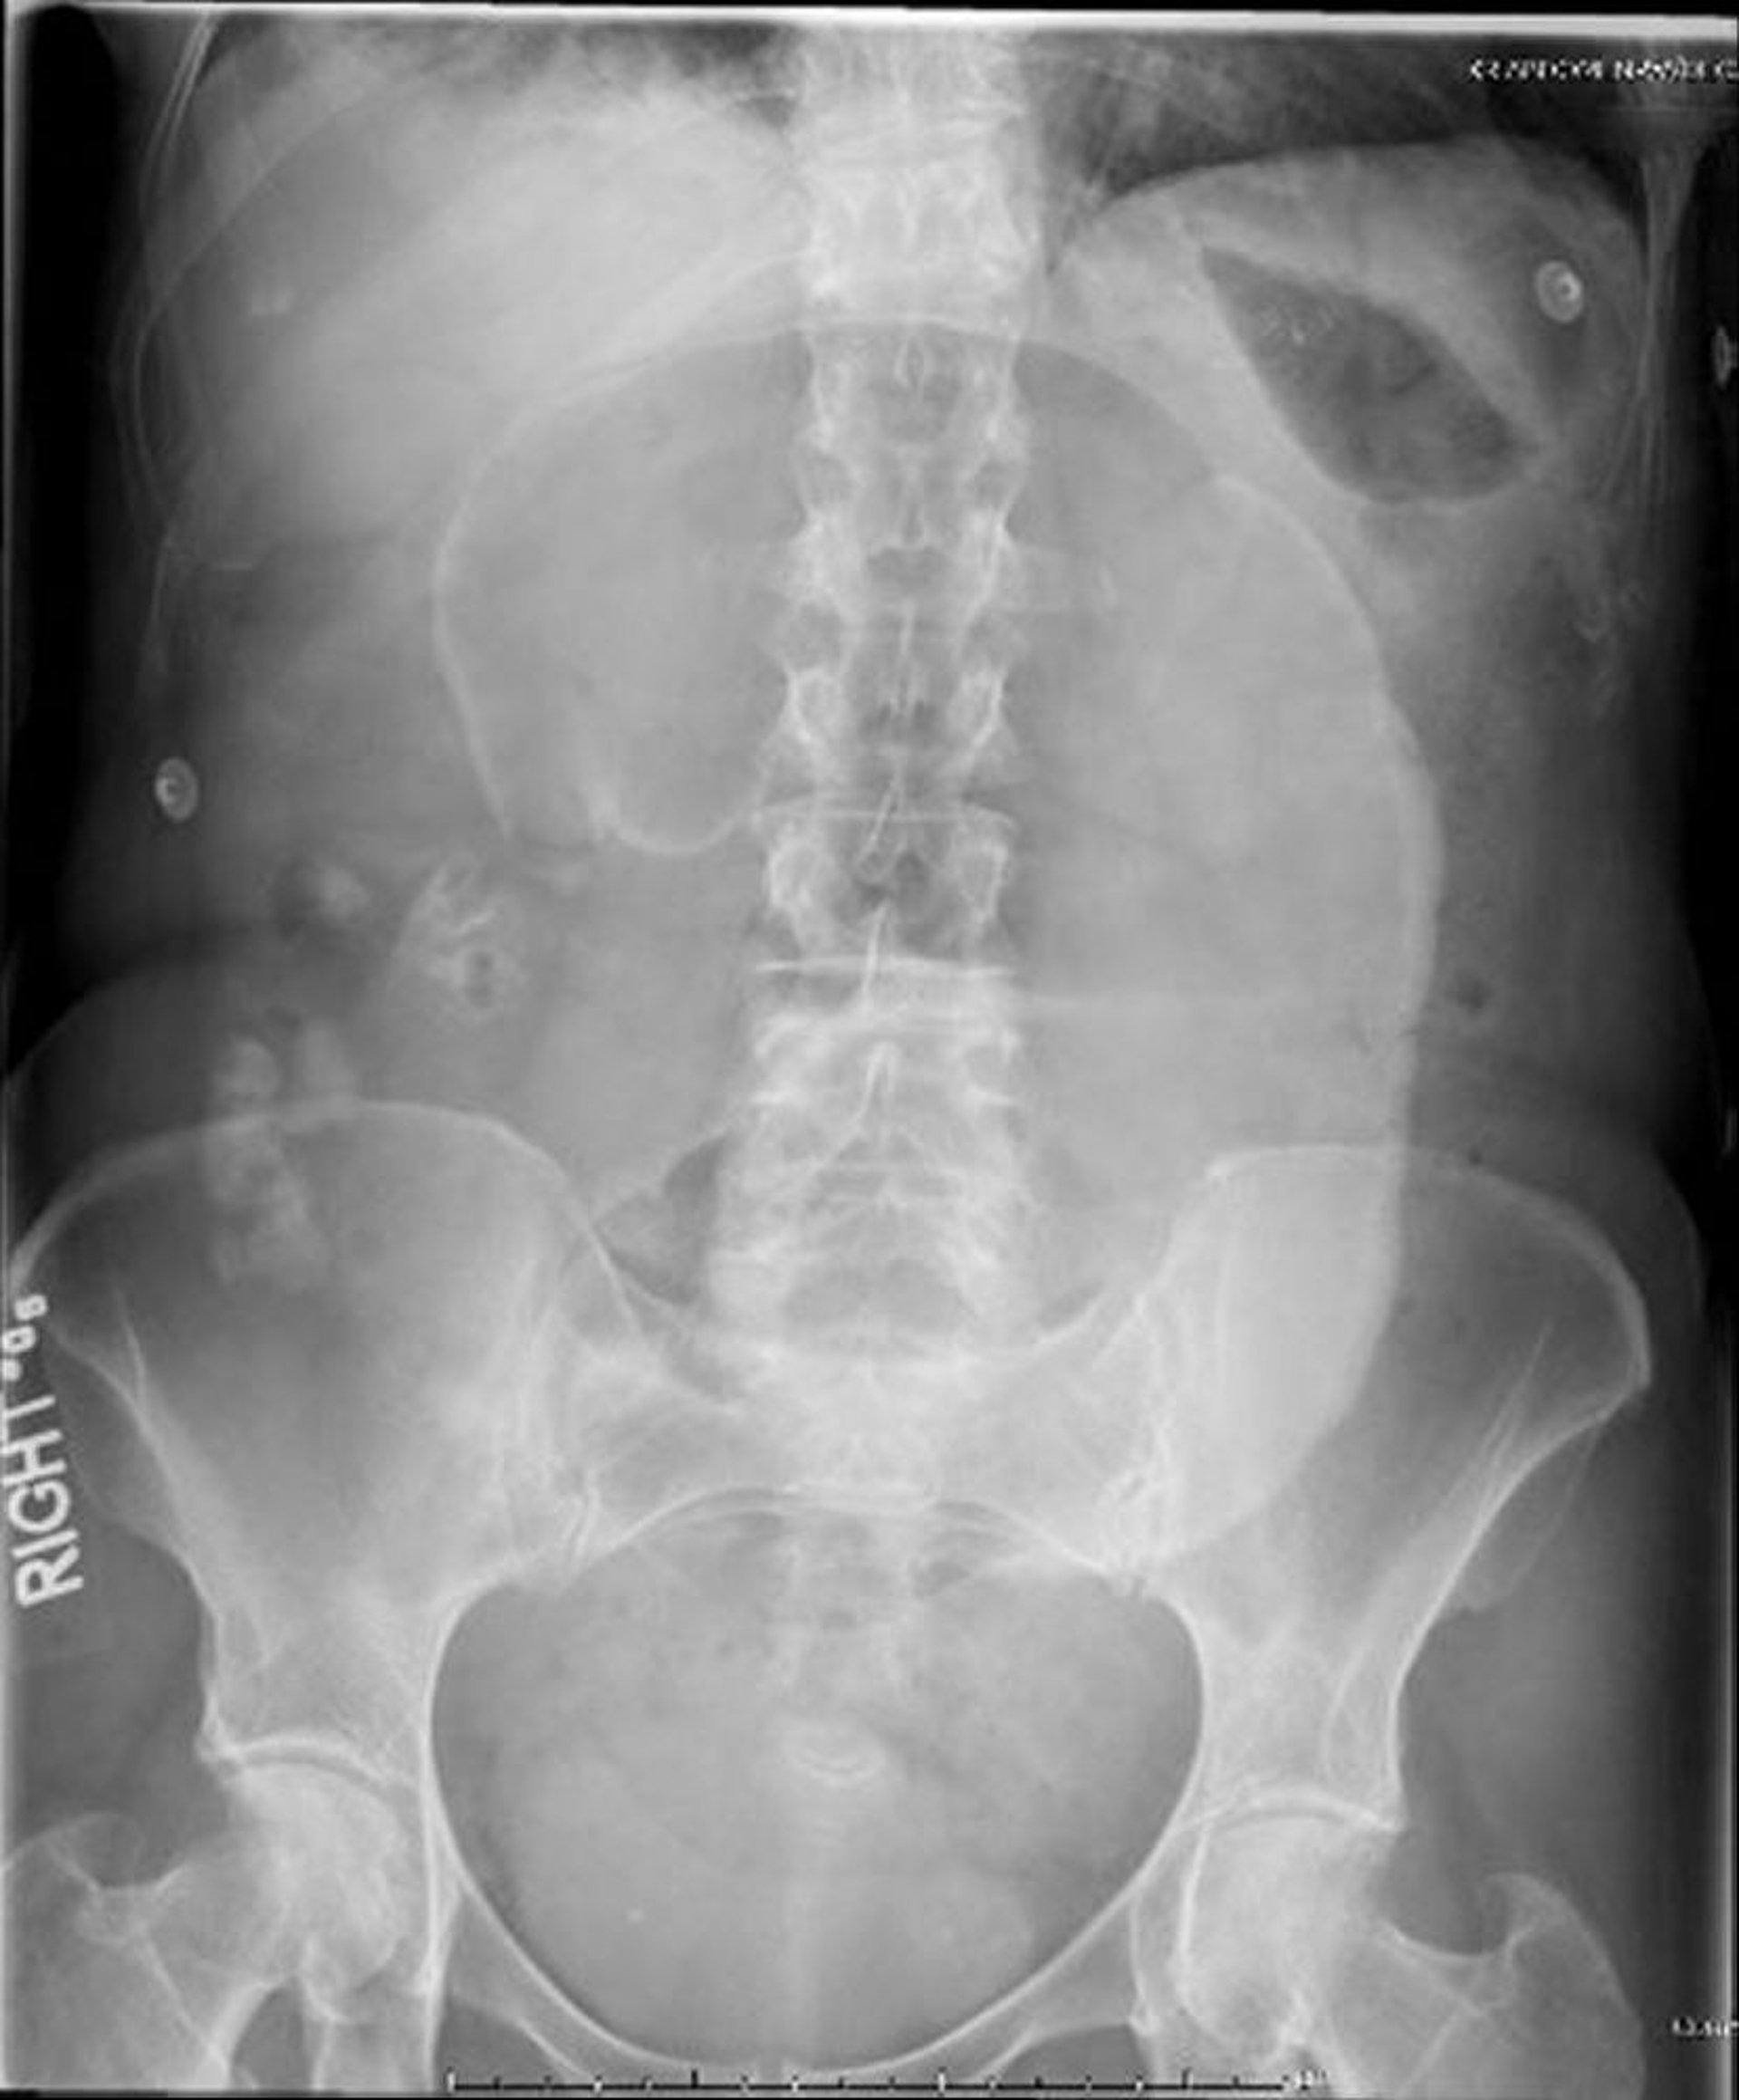

Vólvulocecal (radiografia abdominal)

Nessa radiografia abdominal, o ceco entrelaçou-se com o mesentério, fazendo com que um "grão de café" dilatado se projetasse em direção ao hipocôndrio esquerdo.

Image provided by Parswa Ansari, MD.